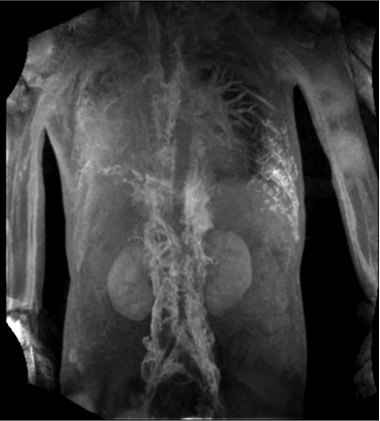

乳糜胸水-腹膜后来源 Chylothorax - Retroperitoneal Flow

腹膜后灌注 Retroperitoneal Perfusion

乳糜胸水 腹膜后来源 Chylothorax - Retroperitoneal Flow